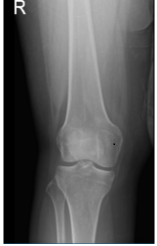

X-ray results showed that there are no significant degenerative changes and there are no fractures. The patient was advised to take an MRI in order to show the reason which caused pain in her knee.

Right Knee X-ray